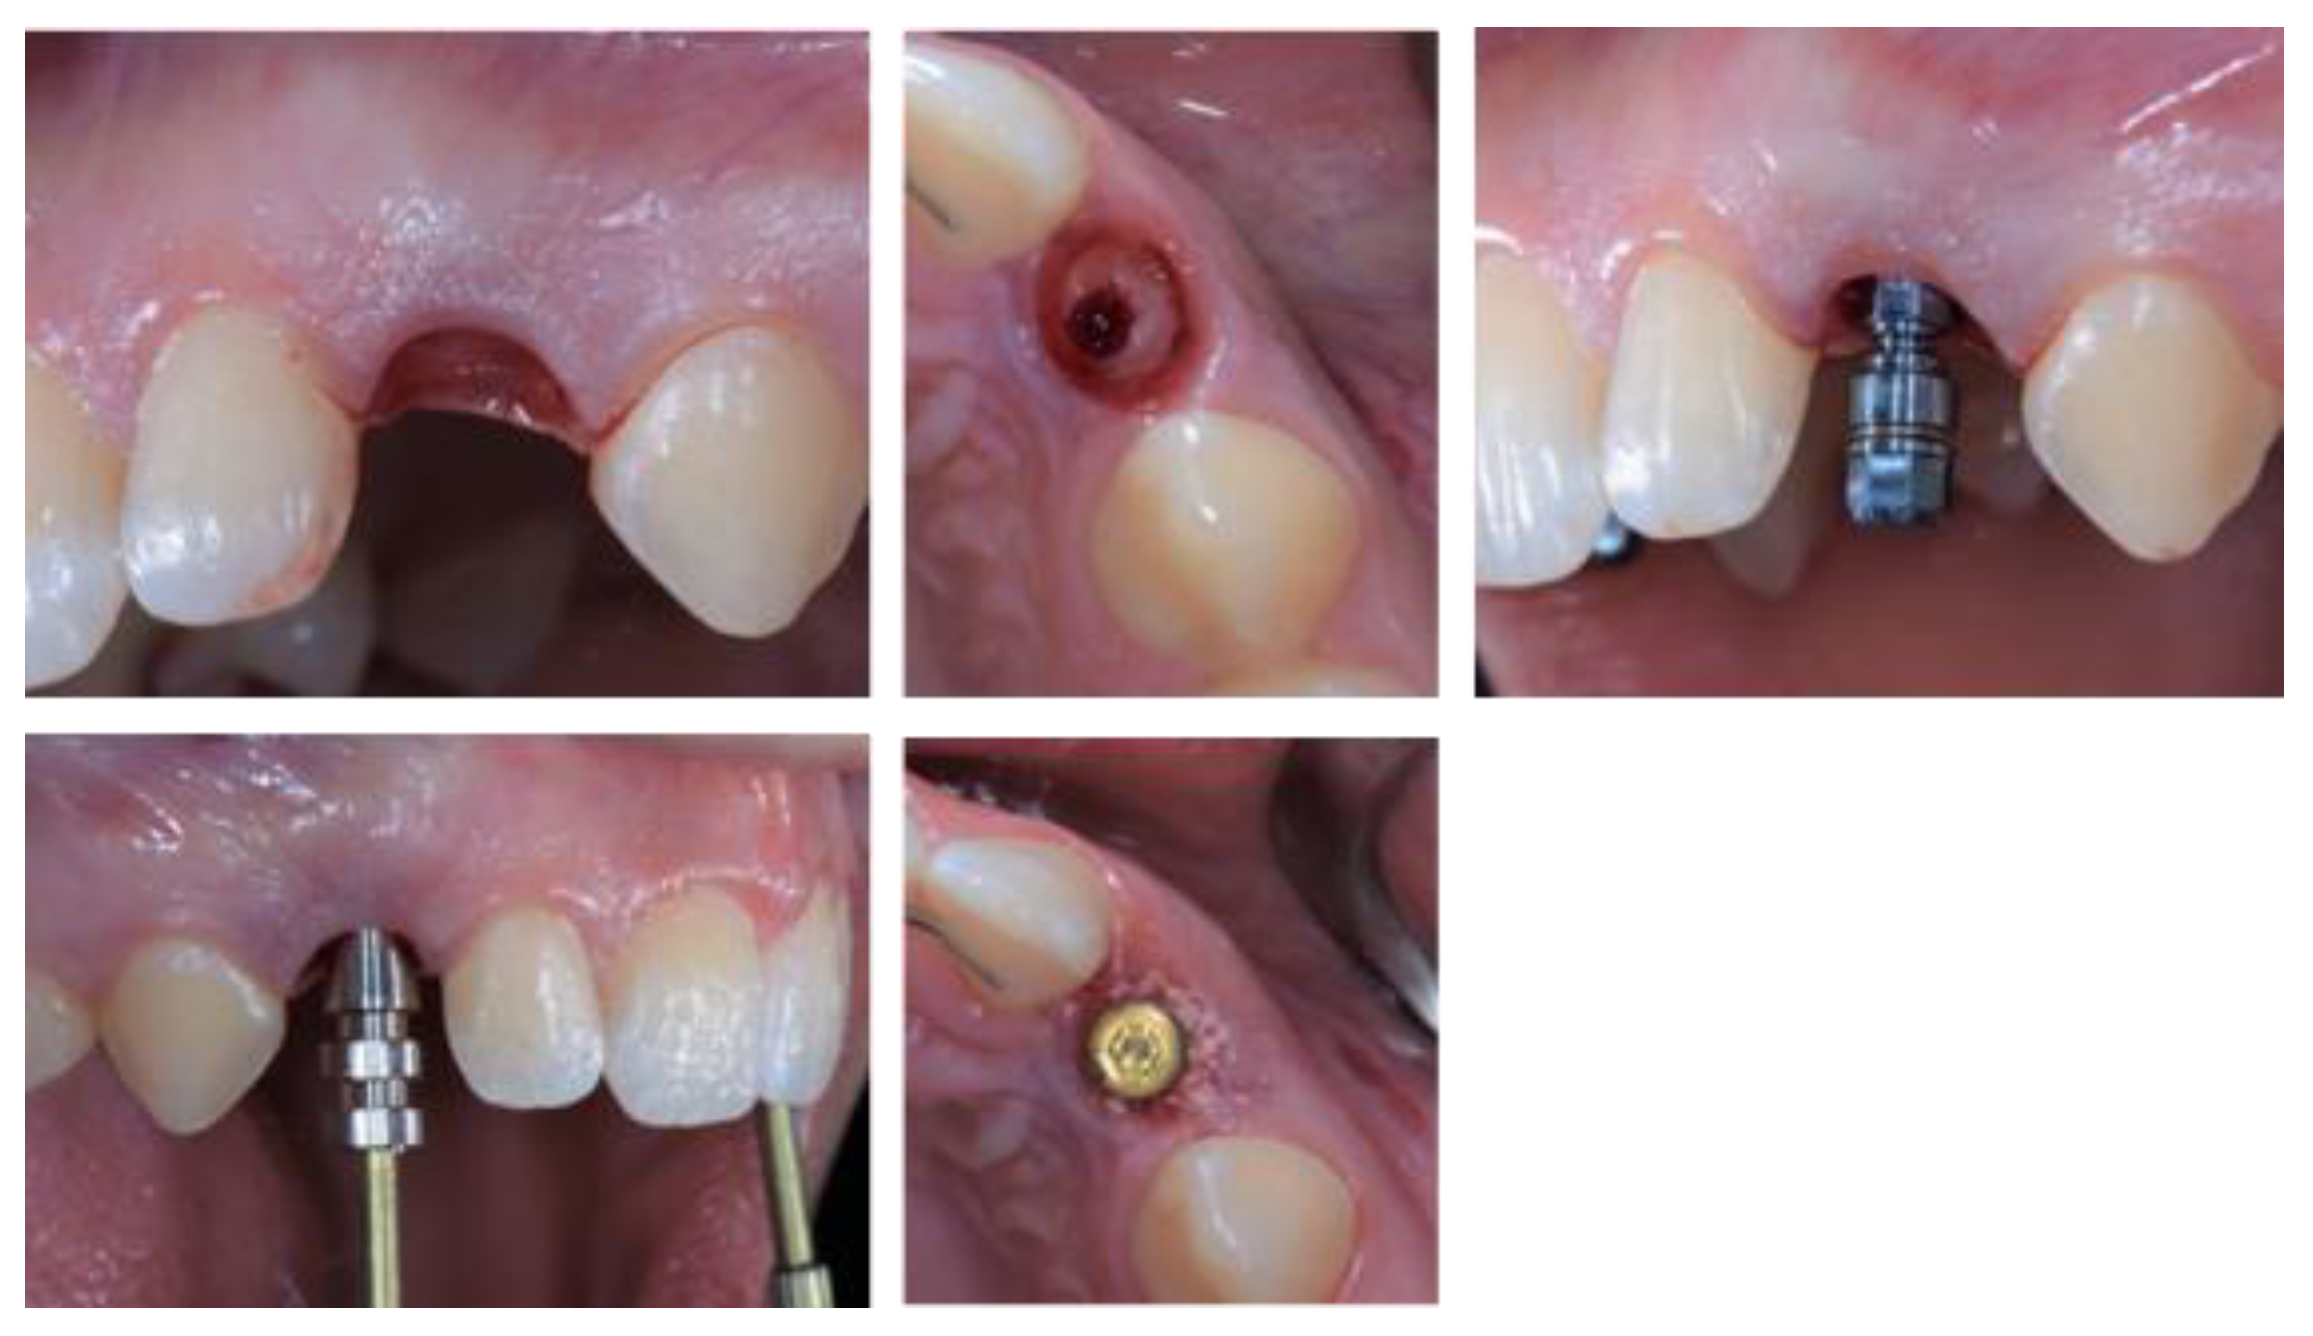

2.5. Individual Cases Description

- Case 1:

- Case 2:

- Case 3:

- Case 4:

- Case 5: